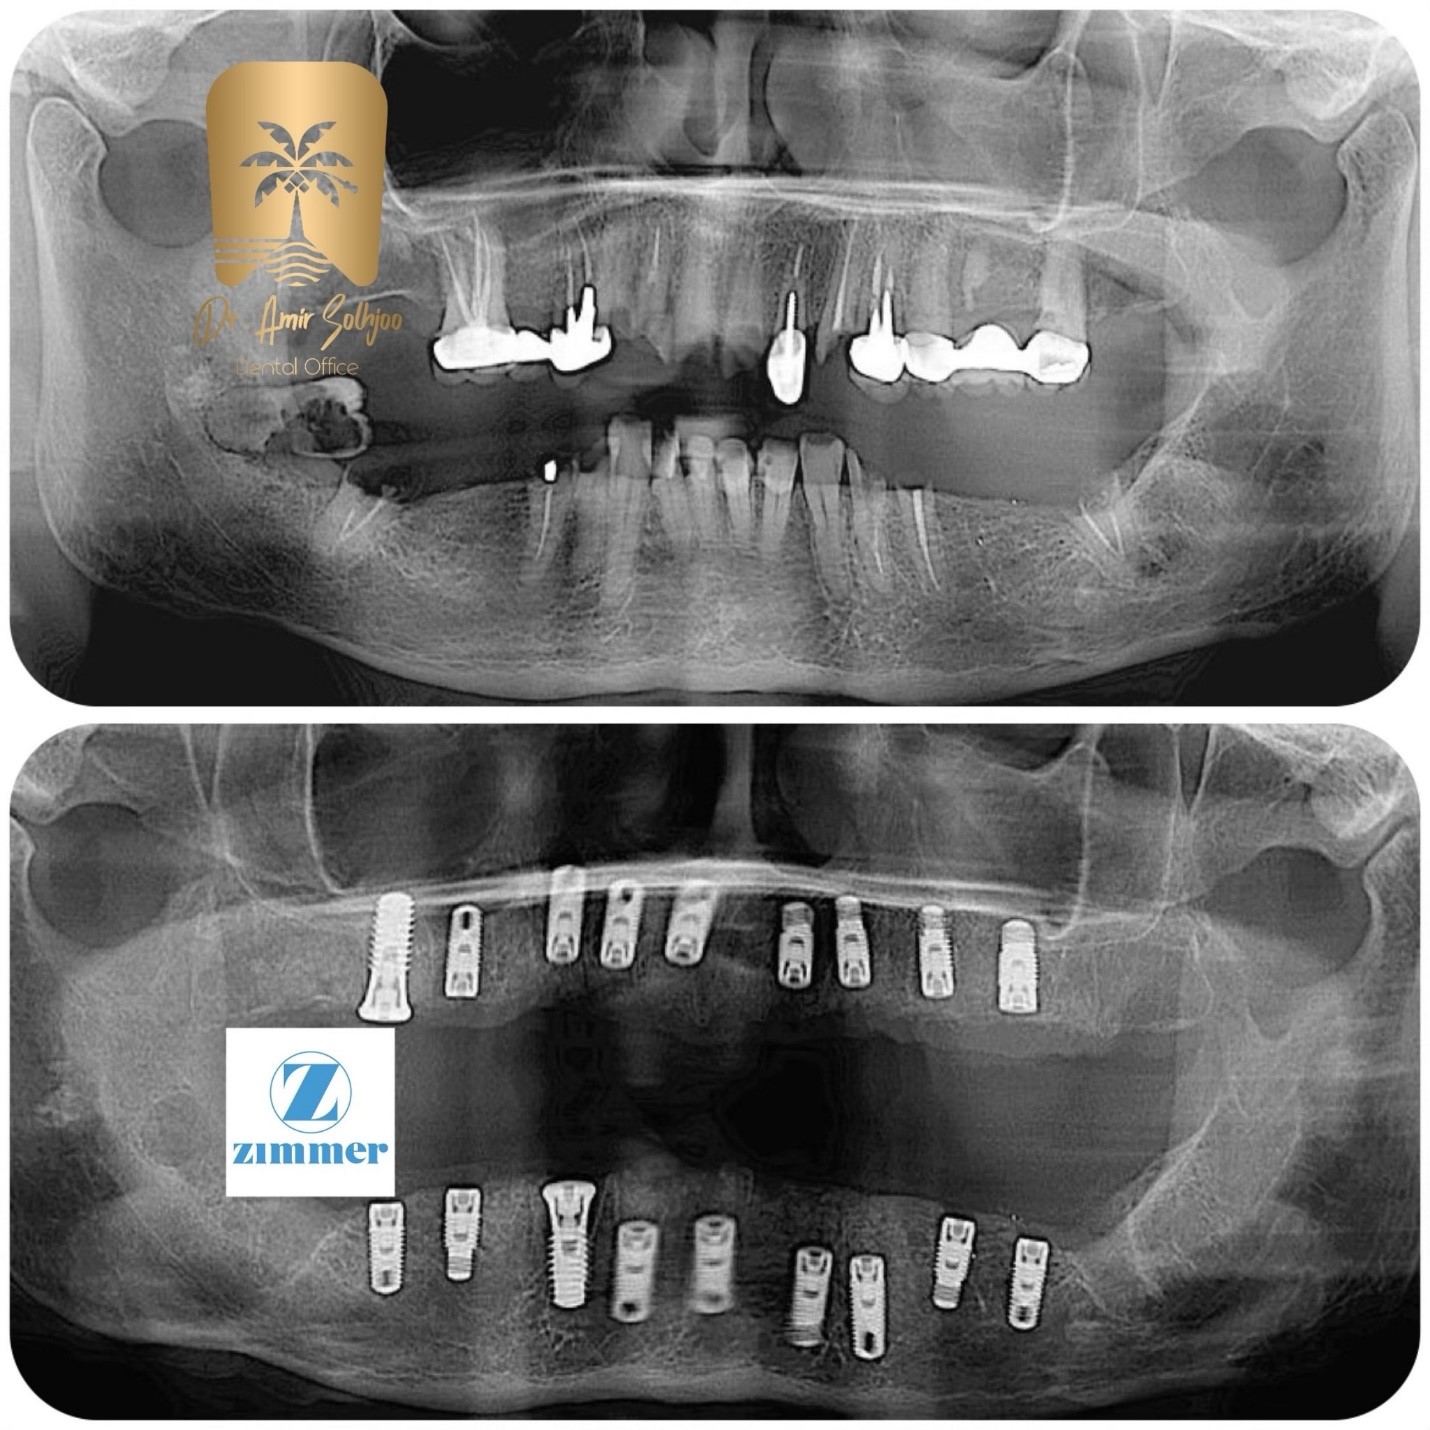

يرجع جزء كبير من سعر الزراعة الكاملة إلى معرفة الجراح ومهارته وخبرته. إن أخصائي زراعة الأسنان الماهر الذي يتمتع بسنوات من الخبرة، والذي يستخدم التقنيات المتقدمة والبرمجة الرقمية، سيحصل بطبيعة الحال على راتب أعلى من طبيب الأسنان العام. هذا الجزء هو في الواقع تكلفة الضمان للقيام بالعمل بدقة ونجاح. يقلل خبراء الدكتور أمير صلاحجو من مخاطر الخطأ باستخدام تقنيات مثل الجراحة الموجهة. العلامة التجارية للزرعة وجودتها: من Zimmer إلى Megagen

تعد العلامة التجارية لقاعدة التيتانيوم أحد المتغيرات الرئيسية في سعر الغرسة الكاملة. العلامات التجارية ذات الشهرة العالمية التي تتمتع بدعم بحثي قوي تكلف أكثر، ولكنها تزيد بشكل كبير من فرص النجاح والمتانة على المدى الطويل. زراعة زيمر بيوميت: هذه العلامة التجارية الأمريكية ذات التاريخ الطويل، href="https://www.dramirsolhjoo.com/%d8%a8%d9%87%d8%aa%d8%b1%db%8c%d9%86-%d8%a8%d8%b1%d9%86%d8%af-% d8%a7%db%8c%d9%85%d9%be%d9%84%d9%86%d8%aa-%d8%a2%d9%85%d8%b1%db%8c%da%a9%d8%a7%db%8c%db%8c/>يُعتبر أفضل زرع أمريكي في إيران، حيث يعمل مستواه المتقدم على تسريع تكامل العظام وبالتالي الزرع الكامل السعر يقع في فئة أعلى مع العلامة التجارية Zimmer.

مقارنة تقدير سعر الغرسة الكامل بناءً على العلامة التجارية (عام 1404) (أمريكي)الوصفالتكلفة الأساسية للزرعسعر أساسي أكثر تنافسيةسعر أساسي أعلىالفرق بسبب التاريخ والبحث وتكلفة الإنتاجتكلفة الدعامةمتضمنة في بعض العبواتمتضمنة في بعض العبواتربط قطعة القاعدة بالغطاءتكلفة غطاء السيراميكمتوسطة إلى عاليةمرتفعةيعتمد على نوع السيراميك (زركونيا، ديسيليكات الليثيوم)نسبة النجاح طويل المدىمرتفع جدًا (حسب الدراسات)مرتفع جدًا (حسب الدراسات)تم إثبات كلا العلامتين التجاريتين علميًا. المصدر: الأكاديمية الأمريكية لطب اللثةالسعر الإجمالي للزراعة الكاملة (لكل وحدة)من 50 إلى 55 مليون تومانمن 58 إلى 68 مليون التومانلا يشمل العمليات الجراحية التكميلية

للحصول على تقدير حقيقي وشخصي للزراعة الكاملة السعر، أنت بحاجة إلى مشورة الخبراء والفحص. فقط بعد فحص حالة عظم الفك باستخدام الصور الشعاعية والأشعة المقطعية، يمكننا تقديم سعر زراعة كامل دقيق ونهائي.